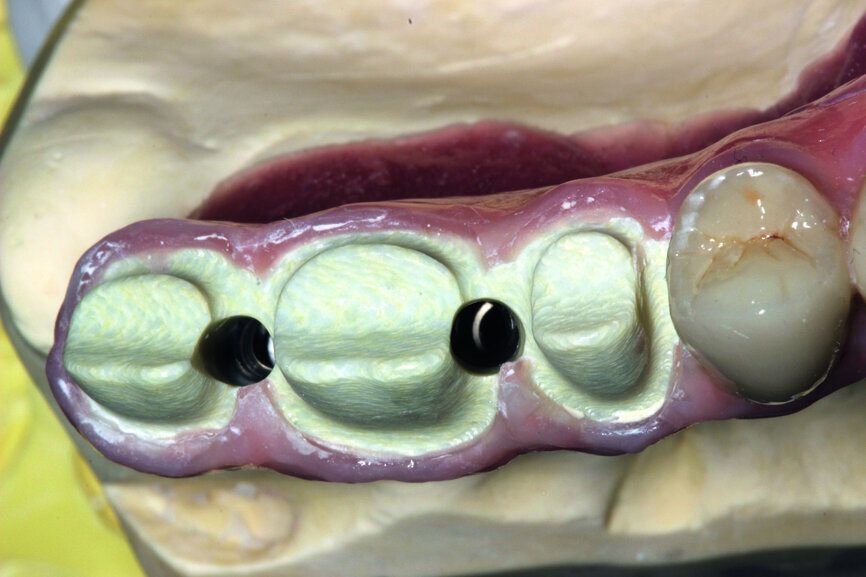

Fig. 12: Test of the construction within the oral cavity—visible opening for screws.

Fig. 21: Openings for screws are located before placing the crowns.